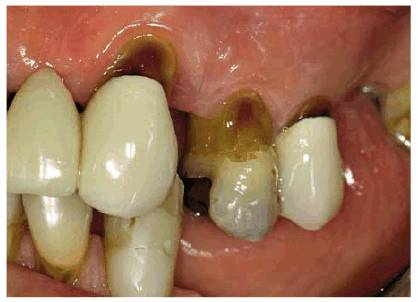

patient (Figures 17-1A to

C

Figure 17-1A to C: These photographs illustrate the complex dental condition of a 71-year-old male: (A) The palatal cervical regions of the maxillary anterior teeth exhibit sharp, wedge-like lesions that are characteristic of abfraction. These areas would be difficult, if not impossible, to have resulted from toothbrush abrasion. (B) The buccal aspects of the maxillary posterior teeth show smooth, concave configurations that are consistent with toothbrush abrasion and/or erosion. (C) The buccal surfaces of the mandibular teeth have lesions that possess components of both abfraction (sharp margins in the occlusal regions) and abrasion (concave geometry and gingival recession in the cervical regions).